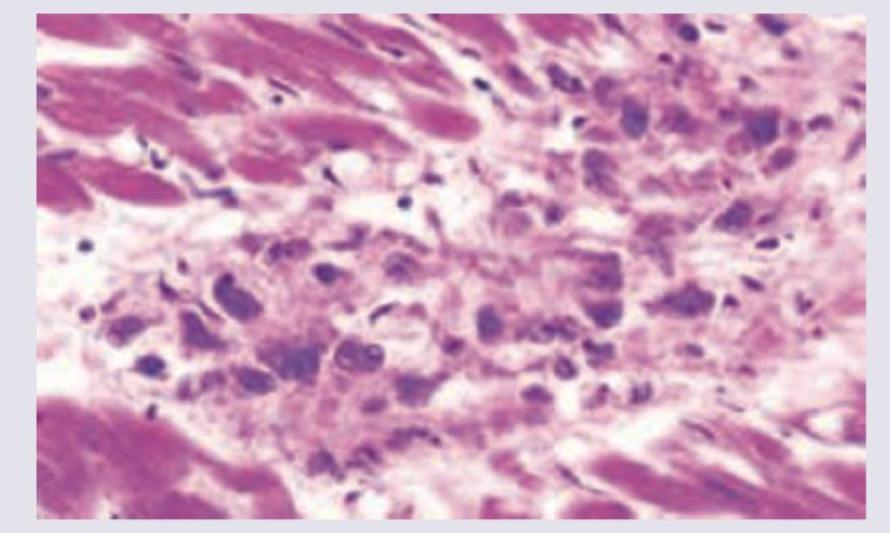

A patient presented with mitral valve stenosis, identify the diagnosis from the mitral valve histopathology depicted below. (AIIMS Nov 2017)

Explanation: ***Rheumatic heart disease*** - **Rheumatic heart disease** is the most common cause of **mitral valve stenosis** and is characterized by **fibrosis** and **calcification** of the valve leaflets, often with **commissural fusion** [1]. - Histopathology would show features like **Aschoff bodies** (granulomas with Anitschkow cells) in the acute phase [3], and later **fibrous thickening** and **neovascularization** of the valve [1]. *Tuberculosis* - While tuberculosis can affect the heart (tuberculous pericarditis or myocarditis), it is an **extremely rare cause of isolated valvular stenosis**. - Histopathology would show **caseating granulomas** with **Langhans giant cells**, which are not typical findings in primary valvular stenosis. *Myxomatous degeneration* - **Myxomatous degeneration** primarily affects the **mitral valve**, leading to **mitral valve prolapse** and **regurgitation**, not stenosis. - Histopathology shows **accumulation of proteoglycans** and **disruption of collagen fibers** within the valve, making it floppy. *Viral myocarditis* - **Viral myocarditis** is an inflammation of the **myocardium** (heart muscle) and typically leads to **dilated cardiomyopathy** and **heart failure**, not primary valvular stenosis. - Histopathology would reveal **inflammatory infiltrates** (lymphocytes) and **myocyte necrosis**, not changes specific to valve stenosis. **References:** [1] Kumar V, Abbas AK, et al.. Robbins and Cotran Pathologic Basis of Disease. 9th ed. The Heart, pp. 566-567. [2] Cross SS. Underwood's Pathology: A Clinical Approach. 6th ed. Common Clinical Problems From Cardiovascular Disease, pp. 293-294. [3] Kumar V, Abbas AK, et al.. Robbins and Cotran Pathologic Basis of Disease. 9th ed. The Heart, p. 566.